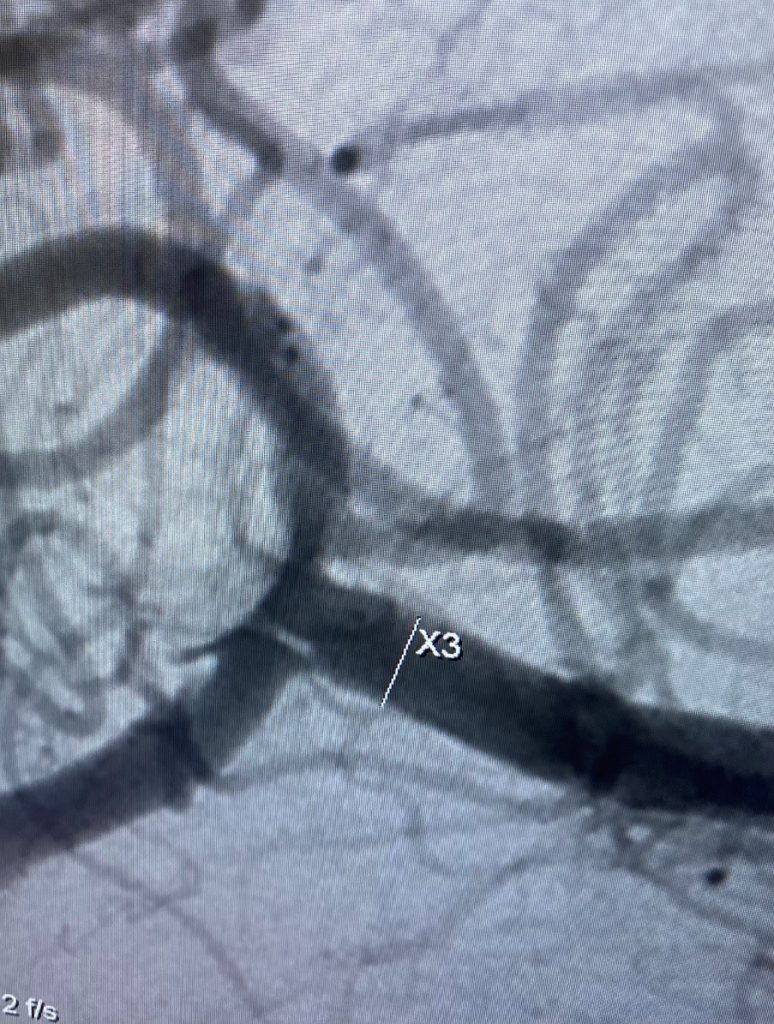

Immediately there is absent filling of the aneurysm except for a minimal filling at the neck which went away at 3 months